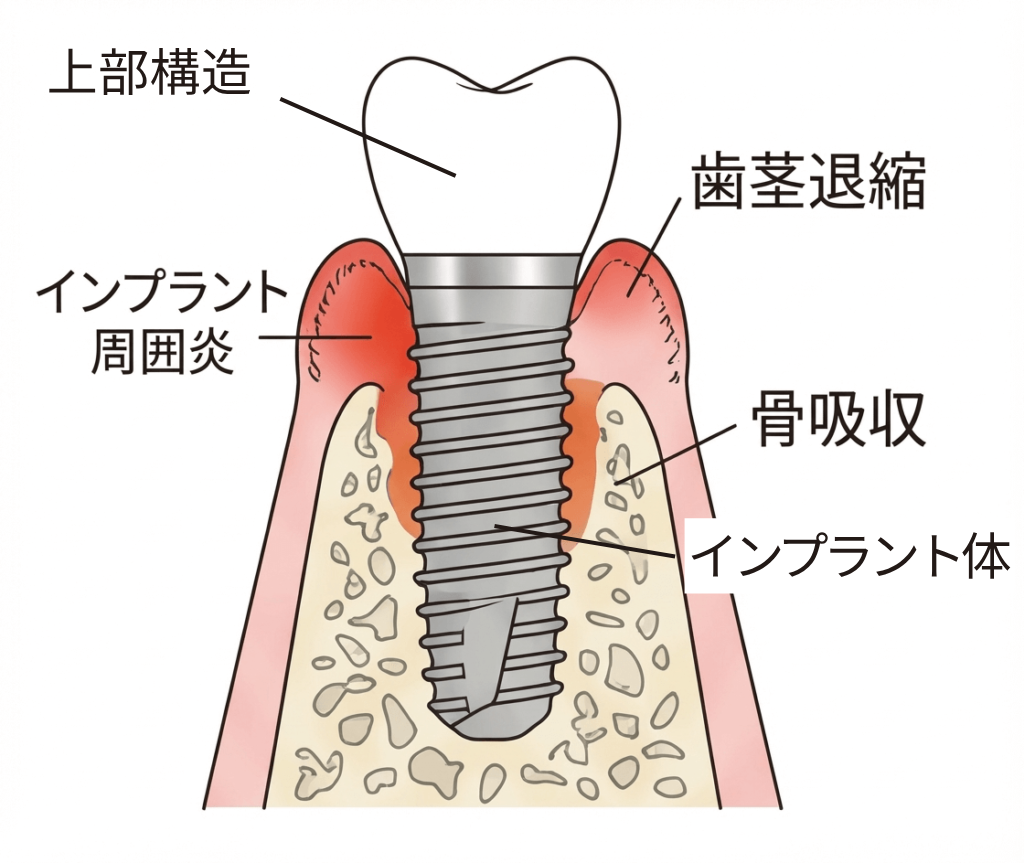

長期的なリスク

- インプラント周囲炎による骨吸収のリスク(定期的なメンテナンスが必要)

- 歯肉退縮による審美的な問題